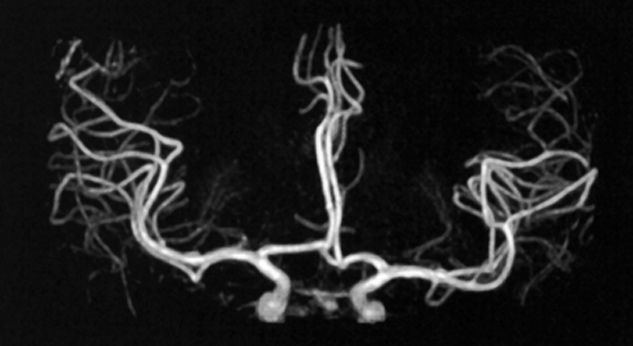

Figure 14-17:

Brain angiogram using TONE and MTC